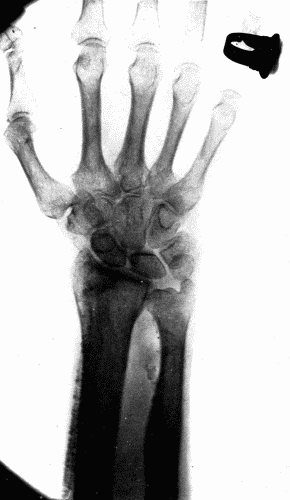

Fig. 6.—Radiogram of a man aged seventy-five, showing calcification of both radial and

ulnar arteries. Fig. 6.—Radiogram of a man aged seventy-five, showing calcification of both radial and ulnar arteries.

Thus the sclerosis of the radials of such an extent that these arteries are easily palpable, appears to be a different process from that of the sclerosis in the aorta, yet fundamentally it is the same. The difference lies in the anatomic structure of the two vessels, and possibly also in the degree of stretching and strain to which the vessels are subjected at every heart beat. In the radial artery the media as usual is affected first. The muscle cells undergo degeneration and either marked thickening takes place or sacculation results, depending upon the severity of the exciting cause. Calcification of the media is common. This occasionally takes the form of rings encircling the vessel, and gives to the examining finger the sensation of feeling a string of fine beads. There may be calcification of the subintimal tissue without deposits of lime salts in the media, but this is more commonly found in the larger arteries. When the calcification occurs in plates through the media, the well known pipe stem vessel is produced. (Fig. 6.)